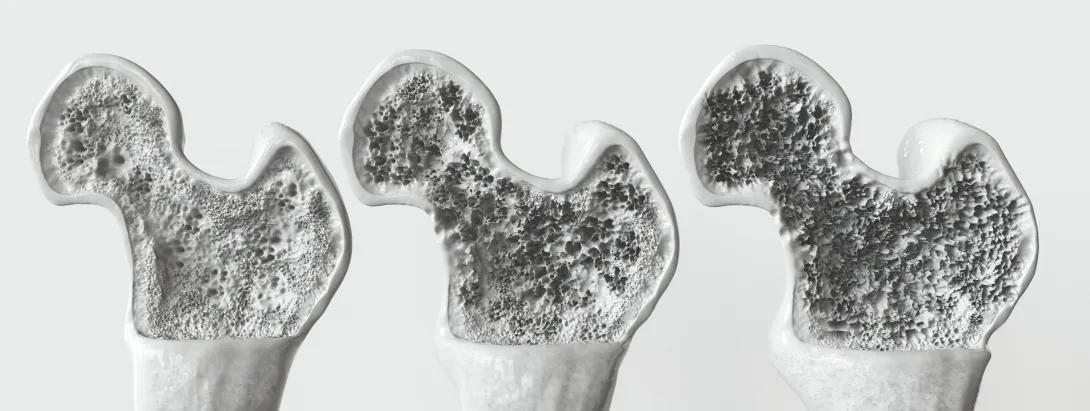

Mensen met een lage botdichtheid hebben mogelijk een verhoogd risico op het ontwikkelen van dementie in vergelijking met mensen met een hogere botdichtheid, volgens een studie die online gepubliceerd werd in Neurology, het medische tijdschrift van de American Academy of Neurology.

De studie is uitgevoerd onder 3651 mensen in Nederland met een gemiddelde leeftijd van 72 jaar, die bij aanvang van de studie geen dementie hadden. Gedurende gemiddeld 11 jaar ontwikkelden 688 mensen dementie (19%). De onderzoekers stelden de botdichtheid vast op basis van röntgenfoto's. De deelnemers ondergingen om de vier tot vijf jaar een interview en deden fysieke tests zoals botscans en testen op dementie. De onderzoekers corrigeerden voor factoren als leeftijd, geslacht, opleiding, aandoeningen en medicijngebruik, en een familiegeschiedenis van dementie.

Uit de analyses bleek dat mensen met de laagste totale botdichtheid 42% meer kans hadden om binnen 10 jaar dementie te ontwikkelen dan mensen in de hoogste groep.

Deze studie bewijst niet dat een lage botdichtheid dementie veroorzaakt. Het toont alleen een verband aan. Nader onderzoek is nodig om het verband tussen botdichtheid en geheugenverlies beter te begrijpen. Het is mogelijk dat botverlies al optreedt in de vroegste fasen van dementie, jaren voordat zich klinische symptomen manifesteren. Als dat het geval zou zijn, zou botverlies een indicator kunnen zijn voor het risico op dementie en zouden mensen met botverlies in aanmerking kunnen komen voor screening en betere zorg.